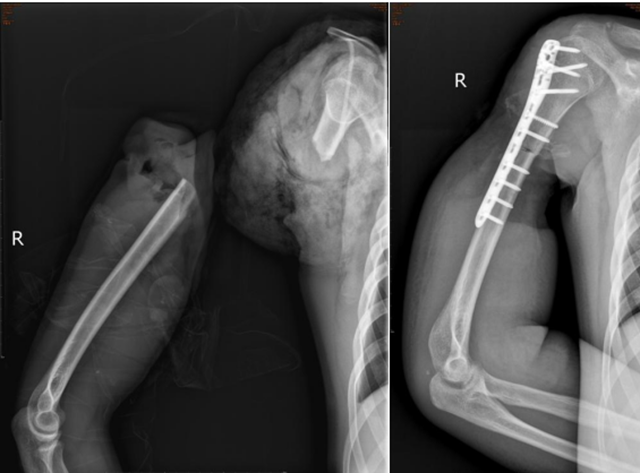

2023年9月的某一天,19岁的李明(化名)在沙石厂干活时,被“输送机皮带”绞伤右上肢,当即致右上臂处完全离断,疼痛剧烈、出血不止。

工友立即拨打120,由120将李明送至西南医科大学附属中医医院急诊科,急诊以“右上臂创伤性切断”收入骨伤科手外·儿骨·烧伤整形组。

值班医生王波接诊处理后,科室副主任陈孝均、医疗组长刘安铭、主治医师黄宇、主管医生王波共同为患者制定了急诊手术方案:右上臂断肢再植+血管移植术,手术历时8小时。

术中及术后予以输血、抗感染、抗血管痉挛、补液扩容等治疗,后期又历经清创、植皮等多次手术,最终为李明保住了右上肢,留住了一个青年人的希望。